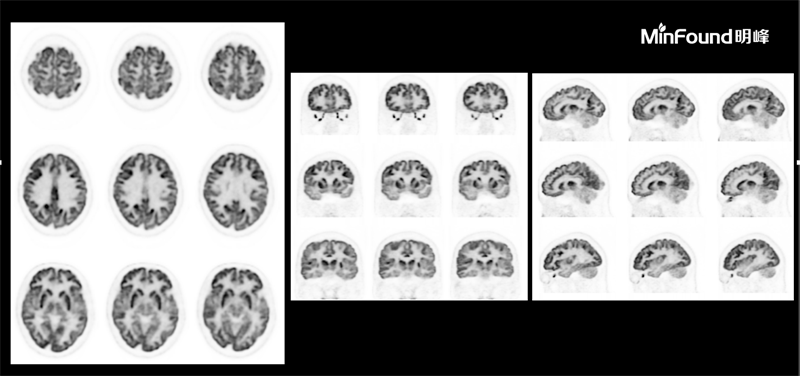

臨床畫廊